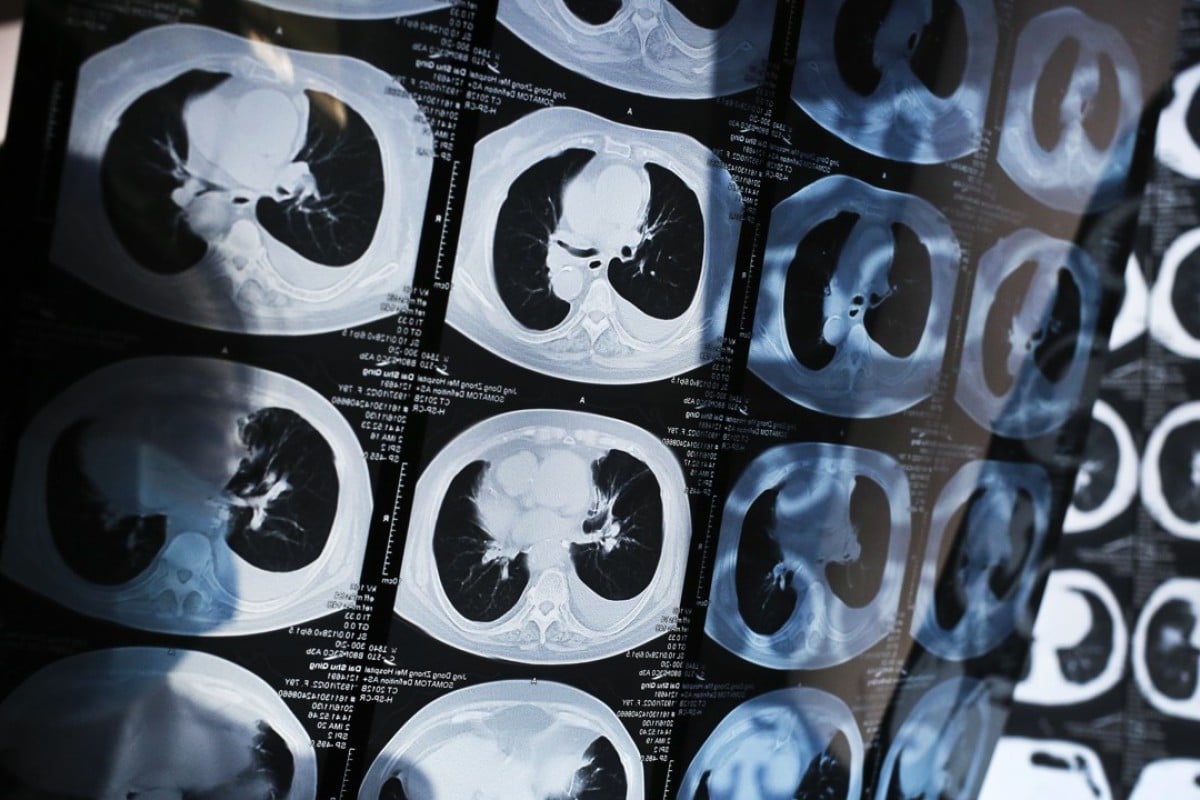

Yitu also unveiled a 4D imaging system for chest CT scans at the RSNA conference, featuring real-time imaging of lungs for detection of nodules and other lesions, including cystic, strip and patchy shadows. This tool is designed as a “clinical assistant” to reduce the workload of radiologists.

Yitu’s new tool highlights an AI application area in which China is strong – in part because of the country’s AI drive but also because the country is home to one in every five cancer patients globally, according to government statistics. Photo: SCMP